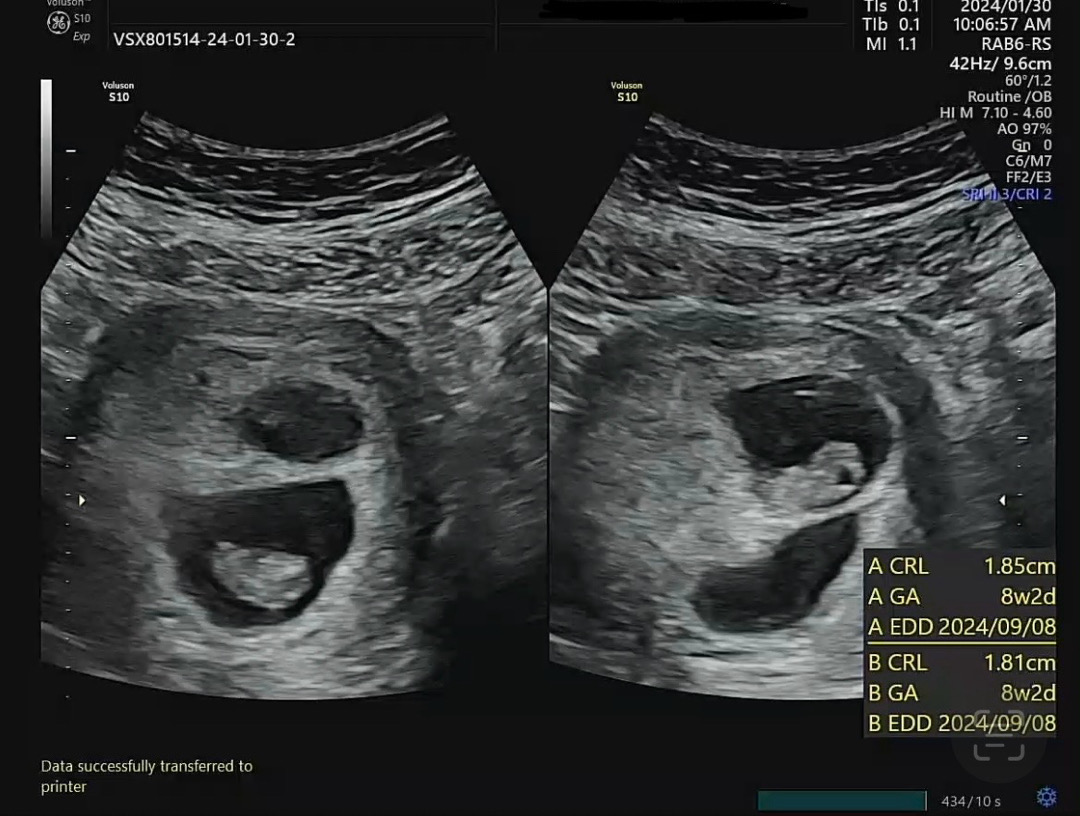

저는 이란성 쌍둥이 맘이예욤! 현재 8주4일 입니다 ㅎㅎ 보건소에서 받아왔던 엽산이랑 비타민D만 먹고 있는데 5000IU인데도 요번 피검사에 비타민D 부족이라고 하네요ㅠㅠ 다른 산모님들 보면 영양제 많이 챙겨드시던데 다들 뭐뭐 챙겨드시나요? 제가 넘 안먹는 것 같아서요ㅠㅠ 글고 혹시 울렁덧 있으신 분들 극복 어케하고 계신가여ㅠㅠ 엄청 예민정도는 아니지만 심할 땐 하루종일 멀미하듯 울렁거리고 어지러우니까 좀 힘드네여ㅠㅠ